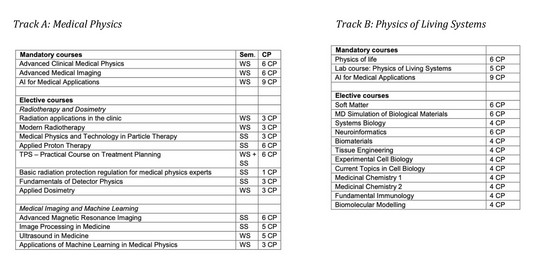

Track A – Medical Physics

The Medical Physics track focuses on the application of physical principles and methods in clinical practice and healthcare. Students gain in-depth knowledge in areas such as radiation therapy, medical imaging (e.g. CT, MRI, PET), and radiation protection. The program prepares graduates for a career as a Medical Physics Expert (MPE) in hospitals, where they play a central role in patient safety, quality assurance, and the optimization of diagnostic and therapeutic procedures.

In addition, students are introduced to the development and improvement of medical technologies, which opens up opportunities in the healthcare and medical device industry. The track strongly benefits from collaborations with hospitals, clinics, and research institutions, ensuring that theoretical knowledge is always connected to real-world applications. Graduates are thus well equipped for both clinical work and research, as well as for further academic careers such as a PhD.

Track B – Physics of Living Systems

The Physics of Living Systems track focuses on understanding biological processes through the lens of physics. Students learn to apply concepts from statistical physics, nonlinear dynamics, and complex systems to investigate living matter, ranging from molecules and cells to organs and entire organisms.

The curriculum includes training in areas such as neuroinformatics, biochemistry, and biophysics, complemented by modern experimental and computational methods. This interdisciplinary approach equips students to analyze how physical laws shape life and disease, bridging the gap between physics, biology and medicine.

Graduates of this track are well prepared for research in life sciences, biotechnology, and biomedical engineering, as well as for doctoral studies in physics, biology, or related fields. With the growing importance of quantitative approaches in biology and medicine, expertise in the physics of living systems offers excellent career opportunities in both academia and industry.

Area of Specialization (Track A/B)

Here you need to accumulate at least 39 CP from a selected list of courses (some of them ≈ 20CP are mandatory). A comprehensive list of these courses and their description can be found in the latest module handbook. Some of the highlights are

Note: Students should (not mandatory) attend some of the basic lectures in BOTH tracks regardless of their specialization. If you have for instance signed up for Track B, we recommend to also attend a lecture in Track A as part of your electives (e.g. Advanced Clinical MP or Advanced Medical Imaging).